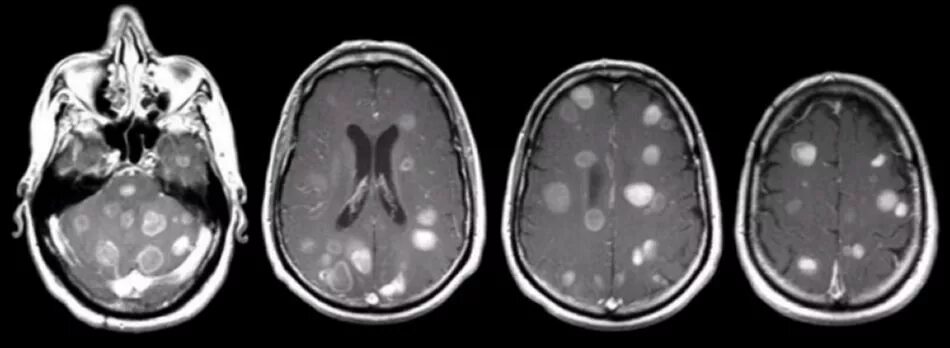

Метастазы головного мозга кт